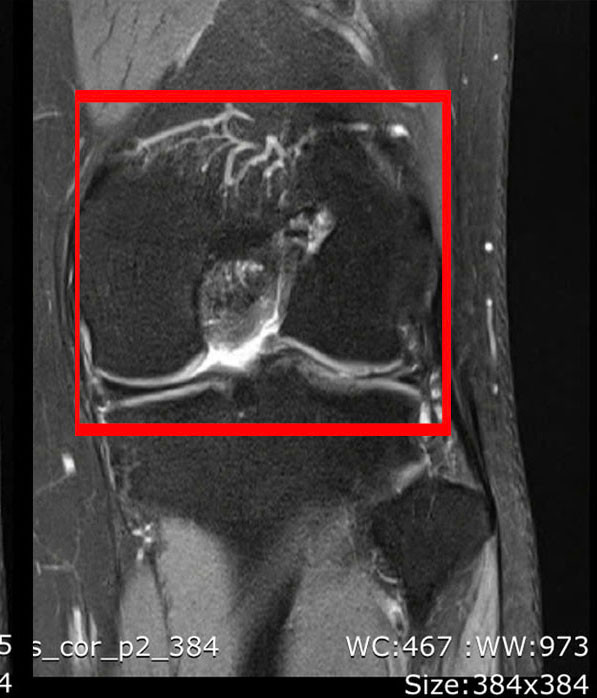

BSCKII Lê Hoàng Văn Hải, Trưởng khoa Chấn thương Chỉnh hình cho biết, qua thăm khám lâm sàng và chụp MRI, chúng tôi xác định bệnh nhân bị đứt hoàn toàn dây chằng chéo trước. Với trường hợp phẫu thuật lần thứ ba này, ê-kíp đã lựa chọn phương pháp tái tạo bằng gân hamstring kết hợp kỹ thuật All-Inside để tăng kích thước mảnh ghép.

![]() |

| Tổn thương dây chằng trên phim chụp - Ảnh BVCC |